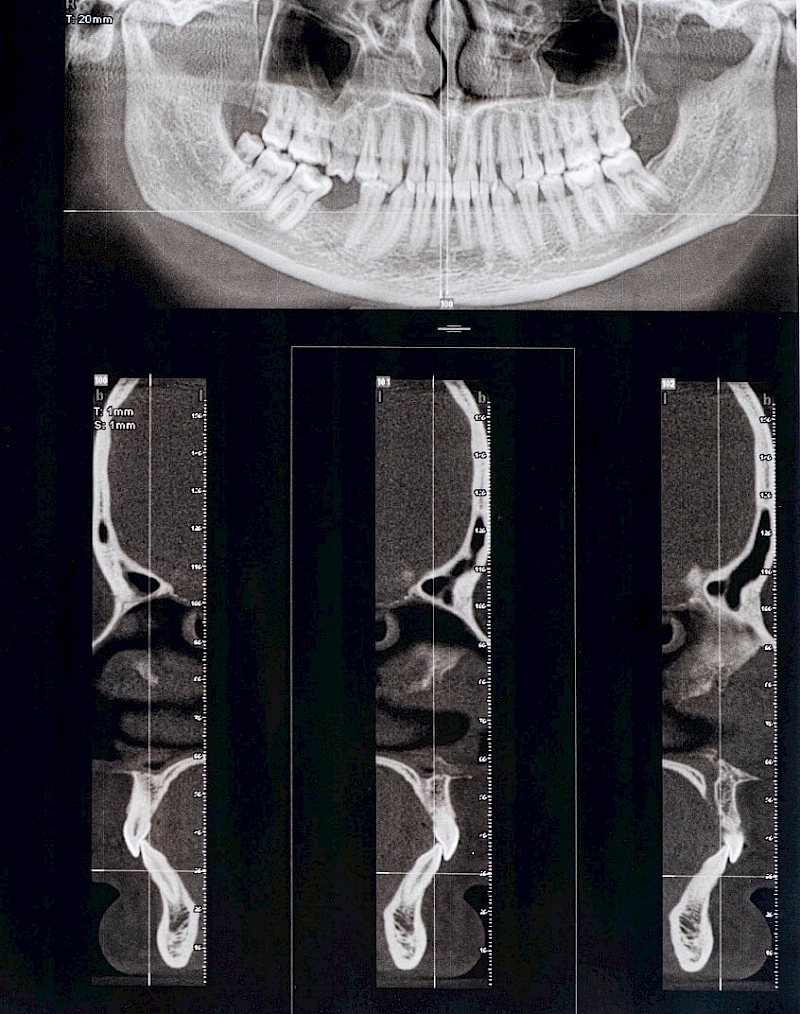

Diş Sıkma - Çene Eklemi Rahatsızlıkları

TME'de diskin deplasmanı ya da kondil ve diskte dejeneratif değişiklikler de oluşabilir. TME'deki klinik semptomlardaki farklılıklar her zaman disk deplasmanı olarak açıklanamaz. Çiğneme kaslarının fonksiyonu ve disfonksiyonu da hesaba katılmalıdır.